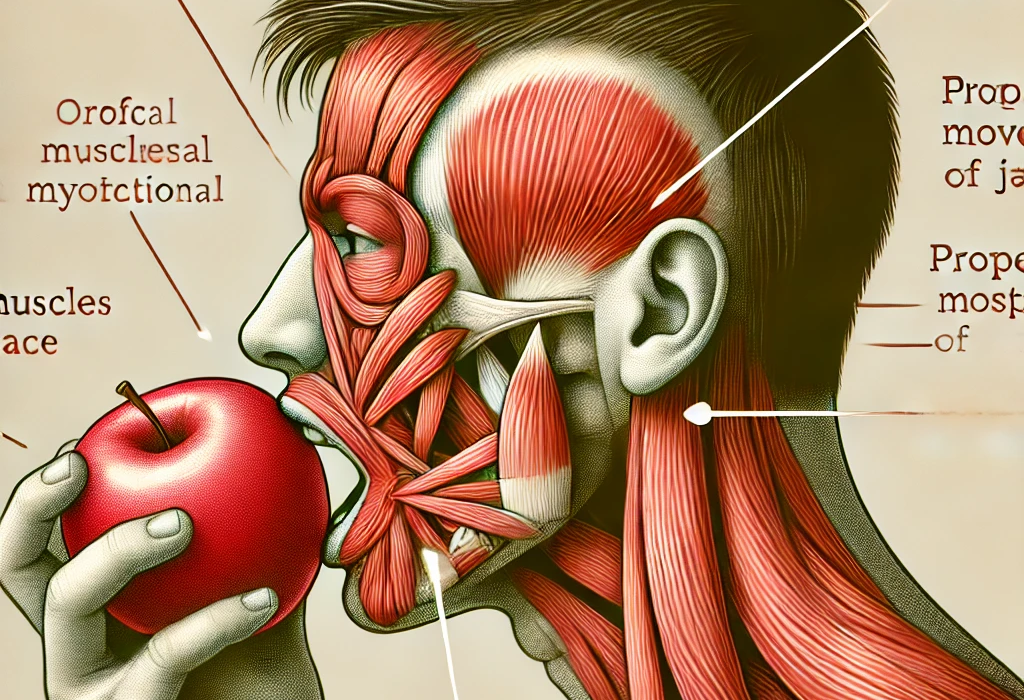

La terapia miofuncional orofacial (OMT, siglas en inglés) es un conjunto de procedimientos y técnicas que facilitan la mejoría de la función bucofacial (Mason RM. 2008)

Desde que comprendí que la terapia miofuncional orofacial se vincula profundamente con el aprendizaje sensoriomotor, ha sido más fácil programar y facilitar habilidades motoras precisas en los pacientes. A través de esta integración, la reeducación de los patrones de movimiento de los músculos de la cara, la lengua y la mandíbula se potencia notablemente. No solo se fortalece la musculatura, sino que también se mejora la coordinación y la percepción espacial de estos músculos, lo que permite lograr una deglución adecuada, patrones masticatorios saludables y una respiración nasal eficaz, esenciales para una función orofacial óptima.